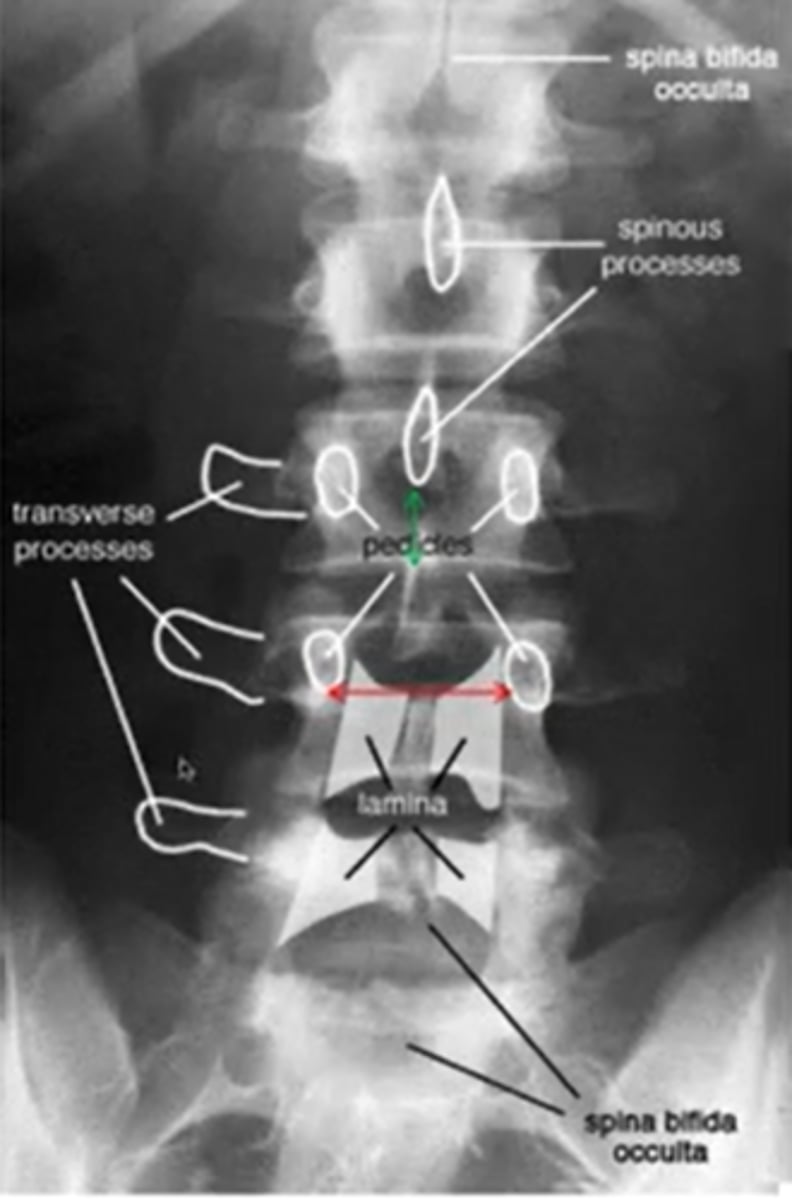

what does a normal lumbar AP look like

what does lumbar spina bifida look like